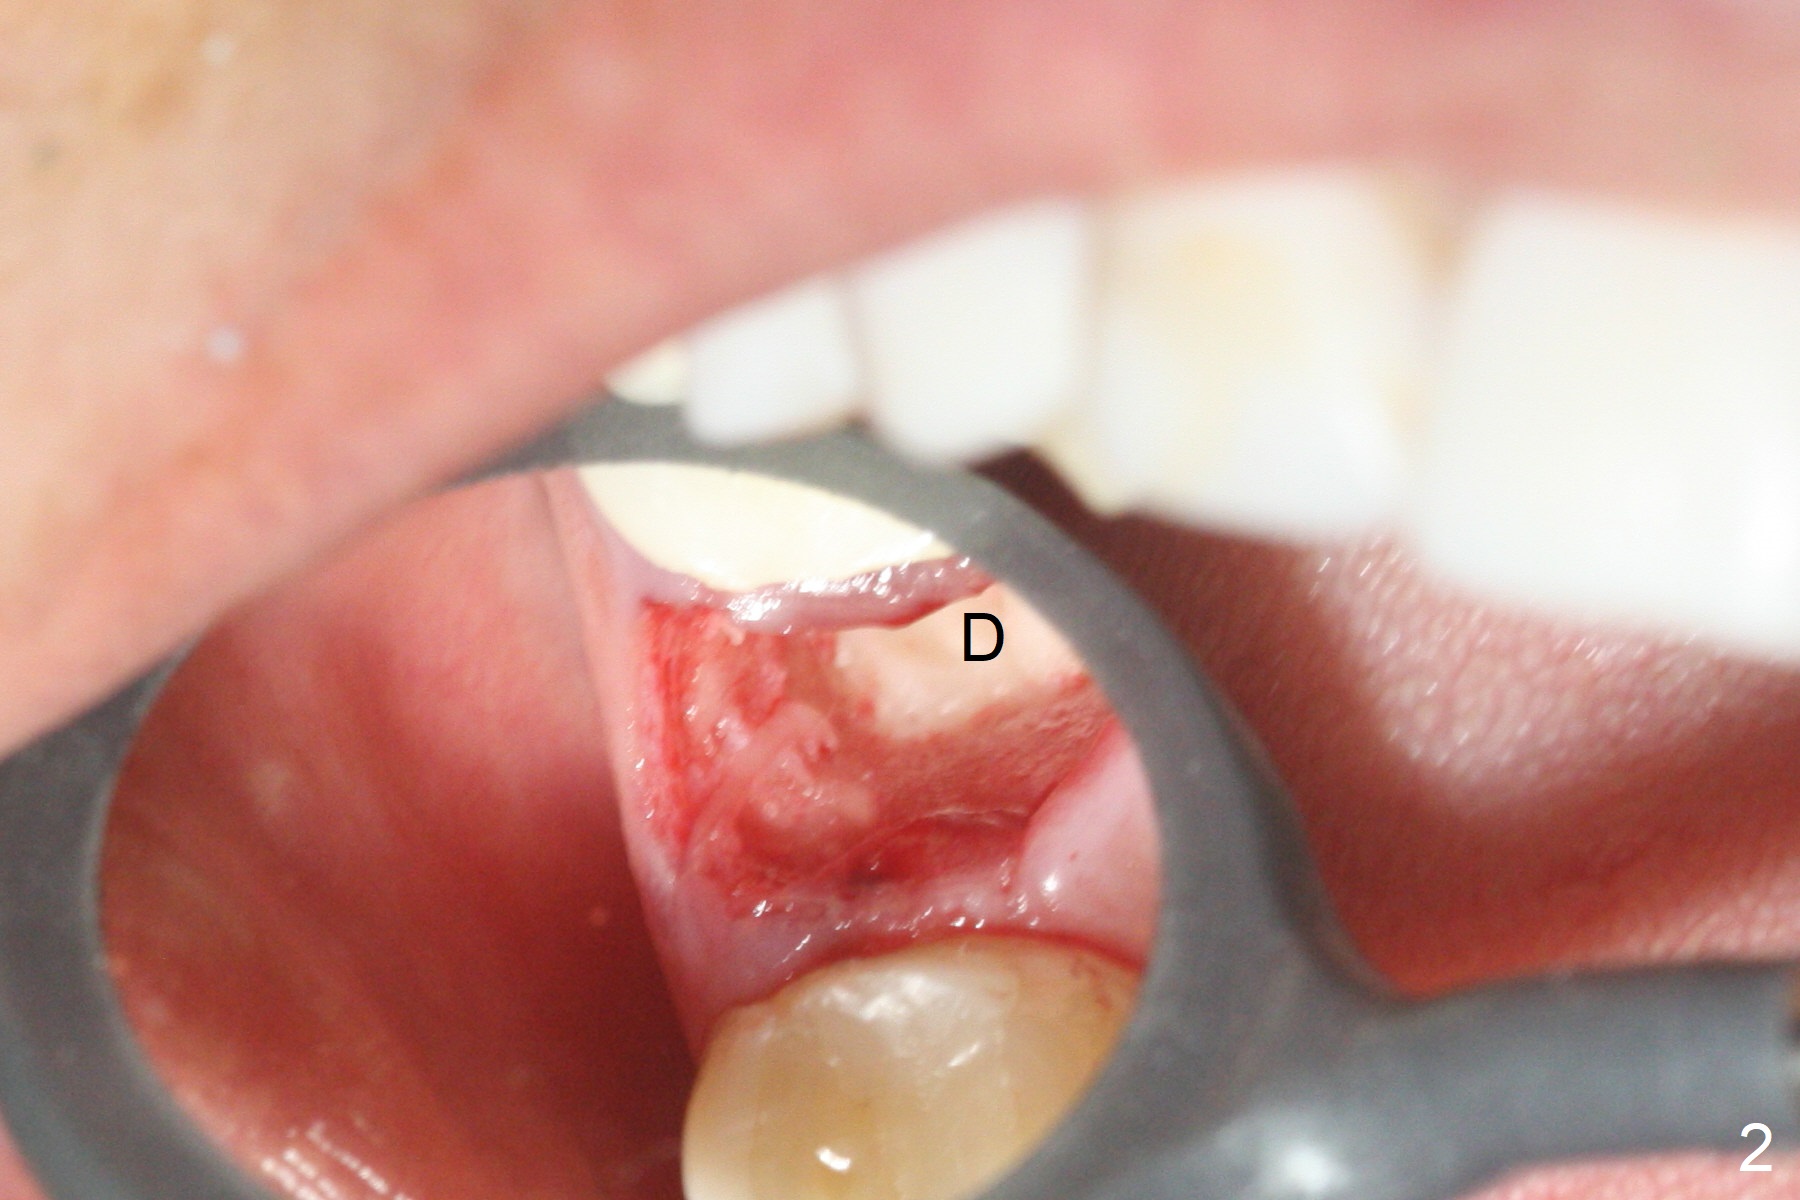

After extraction of the tooth #4 with palatally subgingival fracture (Fig.1 ^), white hard tissue is found in the socket, the density of which is hard (Fig.2 D). When osteotomy passes this portion of the bone (Fig.3 red dashed line), bone density feels reduced suddenly. The osteotomy is moved mesially slightly (Fig.4 (2.7 mm drill)). When a 3.8x15 mm dummy implant is placed with stability, there is an apical space (Fig.5 red dashed line). Therefore the final implant is longer (3.8x18 mm, <30 Ncm, Fig.6, 7). Vanilla graft is placed around the implant and a 4.5x4(4) mm abutment is placed immediately for an immediate provisional (Fig.8). Although the provisional easily dislodges in spite of remake, the implant seems osteointegrated with decreased space 4 months postop (Fig.9). The gingiva is healthy, although it covers the abutment margin partially. Gingivectomy appears necessary for impression.